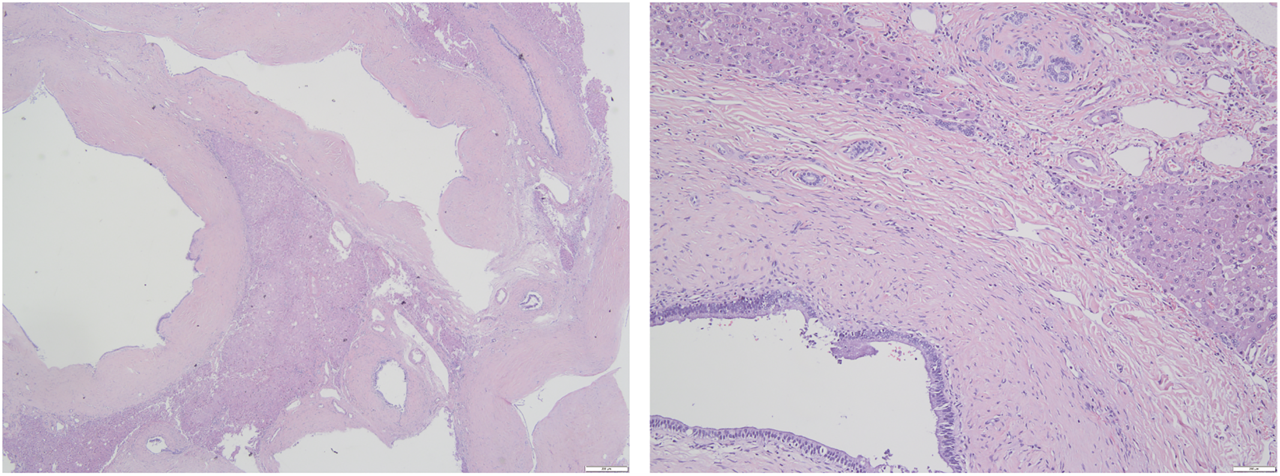

FIGURE 3

Histological findings of the resected lesion tumor (Hematoxylin and eosin staining). (A) The lesion consisted of dilated cystic ducts surrounded by the connective tissue of smooth muscle and capillaries (×20); (B) Ducts are lined by columnar epithelium (×100).

A 37-year old male patient was found to have a multicystic mass with the size 7.7*5.6 cm in the right hepatic lobe incidentally on abdominal ultrasonography. Then he was admitted to our hospital for mild abdominal distention after eating. Neither other significant clinical symptoms nor positive signs were found after further physical examination. Further examinations including liver function、tumor markers and abdominal contrast-enhanced computed tomography (CT) scan were performed. The laboratory results were as follows: alanine transaminase (ALT), 67U/L (normal: 9–40 U/L); carbohydrate antigen 19–9 (CA19–9), 65 U/mL (normal: 0–39 U/mL); other liver function and tumor markers were all in normal range. Abdominal CT revealed a multilocular cystic lesion in the segment VI of liver (Figure 1C). Interestingly, small calcification was found on precontrast CT (Figure 1A) and the septa and peripheral wall within the cystic lesion showed mild enhancement on postcontrast (Figure 1B). Based on these imaging results, we suspected that the lesion could be mucinous cystic neoplasm (MCN) or intraductal papillary neoplasm of the bile duct (IPNB) of the liver before operation. Laparoscopic complete resection of the lesion was performed (Figure 2). Intraoperative findings showed a lesion was grey-white lesion with multicystic surface. No enlarged lymph nodes were found during the operation. The cut surface of the resected specimen has many dilated ductal structures and hepatic parenchyma between these ducts, while bile-like material was observed within some ducts. Intraoperative frozen histopathological examination suggested preliminary diagnosis of biliary cystadenoma. Histopathological findings of formalin fixed paraffin embedded tissue on revealed periductal glands surrounded by connective tissue containing smooth muscle and small blood vessels but no ovarian-like stroma (Figure 3). Immunohistochemistry showed CK19 positivity of the dilated ducts epithelium and the small vessels were positive for CD30. Final histopathological diagnosis confirmed a multicystic biliary hamartoma (MCBH). After the surgery serum CA19–9 level dropped to normal range (28 U/mL) and there were no signs of recurrence 6 months after surgery.

Histologically, MCBH consisted mainly of several ductal structures of different size surrounded with periductal glands and fibrous connective tissues containing small blood vessels and smooth muscle bundles. The dilated ducts contain bile-like material and are positive for biliary-type cytokeratin CK19 (Zen et al., 2006). In 2010, Ryu et al first summarized the imagining features of MCBH: 1) the cut-surface of MCBH showed honeycomb-like appearance and cysts are relatively even in size (above 1 cm); 2) the cystic wall and/or septa within the lesion showed mild enhancement; 3) there was normal hepatic parenchyma within the coalescent lesions; 4) the lesion generally located near the liver surface and protruded from the liver (Ryu et al., 2010). Other reports showed that MCBH also could occur deeper within the hepatic parenchyma (Kai et al., 2008). Cystic liver lesion is the imaging characteristic of many diseases including von Meyenburg Complex (VMC), mesenchymal hamartoma, MCN, Caroli’s disease, and IPNB (Pitchaimuthu and Duxbury, 2017). Because of the overlapping imaging appearances MCBH should also be considered for differential diagnosis of cystic lesion in liver.